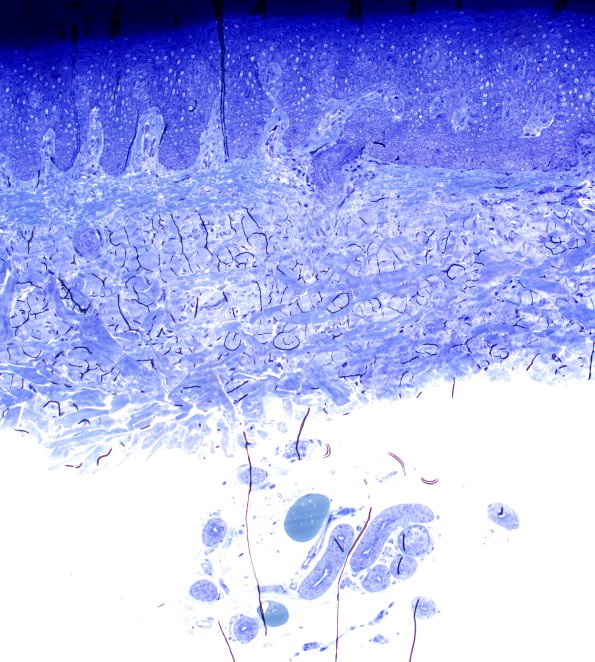

Washington University Experience | METABOLIC | Neuronal Ceroid Lipofuscinosis (NCL) | 2C1 Kuf's Disease (NCL, Case 2) 4X

Low magnification image of toluidine blue stained one micron plastic embedded section showing deep sweat glands. (Plastic section)